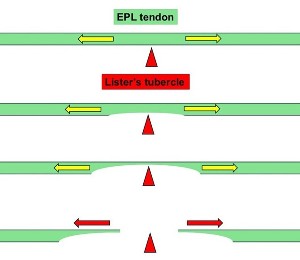

- The EPL = Extensor Pollicus Longus tendon runs along the back of the wrist to the thumb and wraps around Lister’s tubercle, using it as a pulley.

- In some patients, the fracture edges can be rough and they “saw” their way through the EPL tendon.

- This applies particularly when the fracture involves Lister’s tubercle – a prominence on the back of the radius around which the EPL changes direction

- The tendon may wear down and rupture, usually weeks – years after the fracture.

- EPL Decompression - Removing the EPL from the groove adjacent to Lister’s tubercle & placing it superficial to the retinaculum